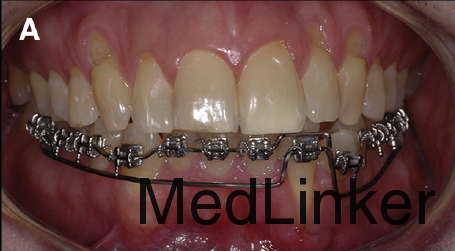

治疗计划:左下2行根管治疗,同时通过正畸重新定位。 治疗:32牙行根管治疗,下颌21*25不锈钢弓丝无力被动入槽稳定下牙弓(避开32牙,不结扎32牙),同时弯制带有根舌向转矩的19*25的TMA弓丝,前段只结扎到32牙,双侧后段插入第一恒磨牙颊管中,每个月加大转矩,持续5个月,在第五个月的时候,可见到32牙根尖已有软组织覆盖。此时上颌上矫治器,排齐整平。总疗程14个月。术后牙周探诊32牙唇侧牙周袋只有1mm。刺激痛症状消失。下颌4-4由16*22不锈钢弯制的舌侧丝保持。1年后复诊,效果仍然稳定。